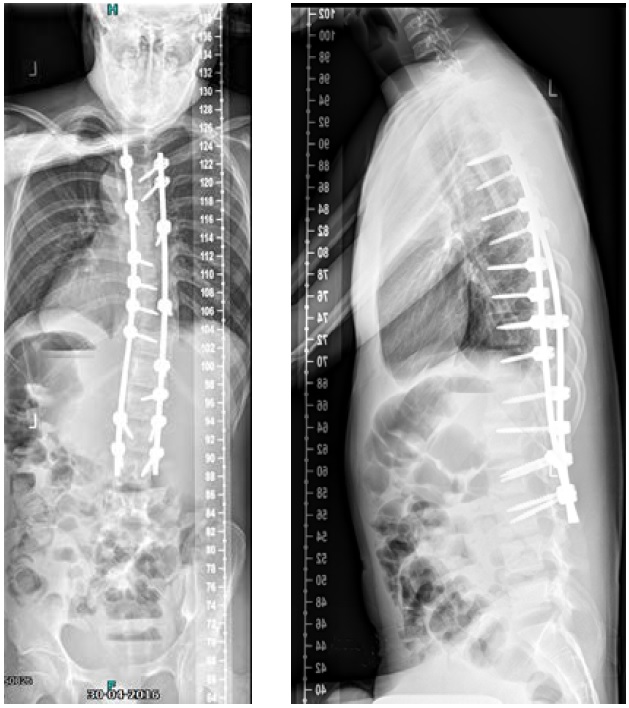

He was scheduled for a posterior deformity correction from T4L3. Under general anesthesia, with IONM (TC-MEP) the deformity was corrected. Intraoperatively, an epidural catheter was placed with the tip at T7 for postoperative analgesia.

Mobilisation started the day after surgery. He was discharged the fourth day after surgery. He returned for scheduled follow-up after 7 weeks (Fig 8). He seemed less agitated compared to the period before surgery. He did not seem to have specific limitations.